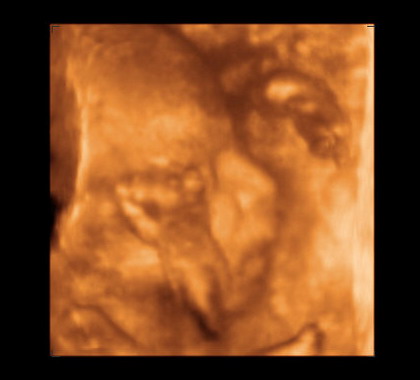

Ez a két értékelhető kép született a kispasiról :wink: Becsült súlya 770 g, és majdnem egy héttel nagyobb az átlagnál. Örülök, mert akkor talán el is indul a kiírás előtt, és akkor van esélyünk simán szülni (túlhordás az első csaszi miatt nem lehetséges).

Szirom! Nagyon édike a kisfiad, először nem tudtam kivenni az alakot, de amikor ráéreztem, úgy megörültem és nem is értem, hogy miért nem láttam először, annyira tisztán látszik. :shock: